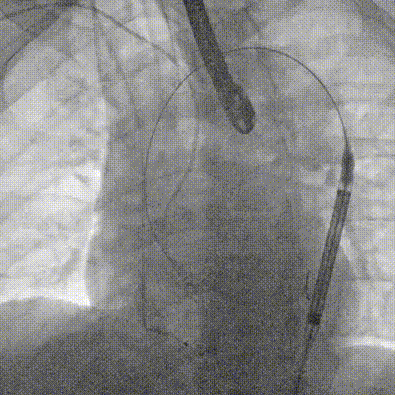

主动脉根部造影

输送系统柔顺过弓